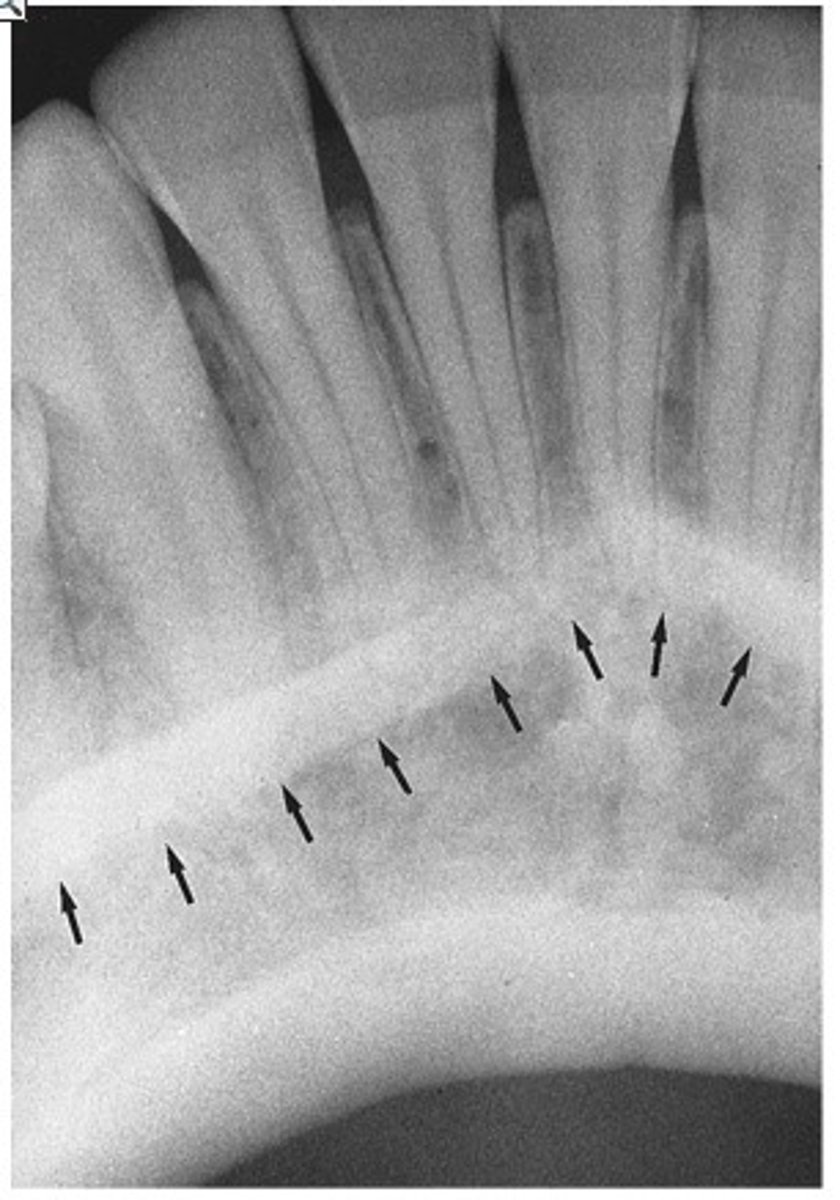

Periodontal ligament space

What is the radiolucent structure seen here?